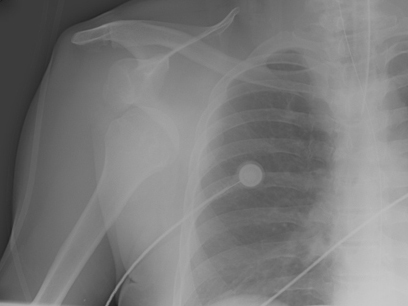

Radiografia com incidência anteroposterior de ombro mostrando luxação anteroinferior

Acervo pessoal do Dr. Paul Novakovich